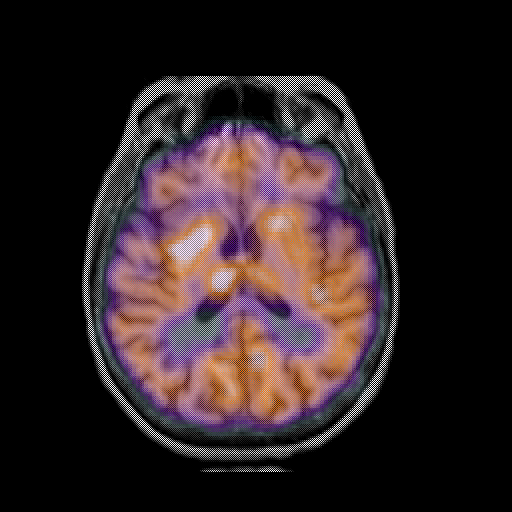

overlay: Slice 30

Slice 30

MRCBFCBF with

T1PDT2T1PDT2